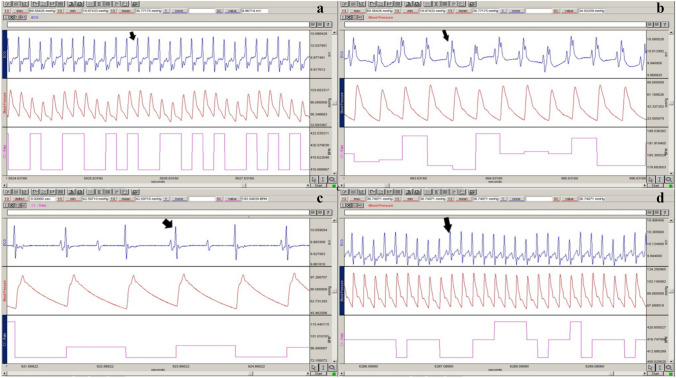

Methods: Wistar albino rats were divided into five groups: control, acute low-dose (ALD, 0.5 mg/kg), acute high-dose (AHD, 5 mg/kg), subacute low-dose (SALD, 0.5 mg/kg for 14 days), and subacute high-dose (SAHD, 5 mg/kg for 14 days). Cardiovascular effects were assessed using echocardiography, hemodynamic and ECG analysis, histopathology, biochemical markers, and LC-MS/MS quantification of JWH-018 and its metabolites in heart tissue.

Results: Acute high-dose JWH-018 caused bradycardia and hypotension, while subacute high-dose increased heart rate but continued to lower blood pressure. JWH-018 induced cardiac arrhythmias, conduction blocks, and ischemic ECG changes, with prolonged QT intervals in subacute high-dose rats. Histopathological findings revealed myocardial infarction-like features, including contraction bands and ischemic damage, particularly in subacute groups. Elevated pro-BNP and triglycerides indicated cardiac stress and metabolic effects. JWH-018 and its metabolites were detected in heart tissue, primarily in high-dose groups.